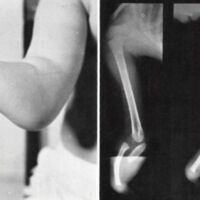

Fig. 5. Left, bilateral ulnar hemimelia. The left is intercalary, since there are five digits; the right is terminal because there are only four digits. Patient has complete anonychia with distinctive pulp prints on the dorsum of the fingers. Right, X-rays reveal complete dislocation of the radiohumeral joints.

Fig. 6. Left, monodigital ulnar hemimelia, incomplete. Right, X-rays reveal proximal remnant of the ulna with a bowed radius.

Dislocation of the radiohumeral joint is rare. One such patient was first seen at four years of age. He has five digits on the left hand and four on the right. There were no fingernails. It is of interest to note that this boy has distinctive prints on both the palmar and dorsal surfaces of his fingers. His radiohumeral joint anatomically is nonexistent (see Fig. 5). The intrinsic muscles of the hands are weakened, and the wrists are unstable. The forearms and hands have been encased in a half-sleeve of plastic attached to crutches (he also has bilateral amelia of the legs). He is now 18 years old and attends a trade school.

Incomplete ulnar hemimelia occurred twice in this series. The proximal portion of the ulna is present, thus affording a normal-appearing elbow joint with an excellent range of motion (see Fig. 6). That child was seen at four years of age and fitted with a standard below-elbow prosthesis, which she is currently wearing.